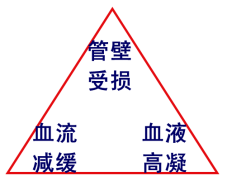

血液在血管内不停流动,为什么会凝固成栓呢?血栓的形成是多种因素作用的结果,国外专家归纳了一下,主要有三方面因素(图3),第一个是血管内膜的损伤,第二个是血液的高凝状态,第三个是血液的流速变慢。这三个原因相辅相成,共同形成血栓。

图3 血栓形成三因素